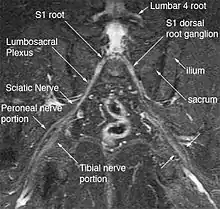

The most significant impact of magnetic resonance neurography is on the evaluation of the large proximal nerve elements such as the brachial plexus (the nerves between the cervical spine and the underarm that innervate shoulder, arm and hand),[9] the lumbosacral plexus (nerves between the lumbosacral spine and legs), the sciatic nerve in the pelvis,[10] as well as other nerves such as the pudendal nerve[11] that follow deep or complex courses.

Neurography has also been helpful for improving image diagnosis in spine disorders. It can help identify which spinal nerve is actually irritated as a supplement to routine spinal MRI. Standard spinal MRI only demonstrates the anatomy and numerous disk bulges, bone spurs or stenoses that may or may not actually cause nerve impingement symptoms.[12][13]

Use of magnetic resonance neurography is increasing in neurology and neurosurgery as the implications of its value in diagnosing various causes of sciatica becomes more widespread.[25][26] There are 1.5 million lumbar MRI scans performed in the US each year for sciatica, leading to surgery for a herniated disk in about 300,000 patients per year. Of these, about 100,000 surgeries fail. Therefore, there is successful treatment for sciatica in just 200,000 and failure of diagnosis or treatment in up to 1.3 million annually in the US alone. The success rate of the paradigm of lumbar MRI and disk resection for treatment of sciatica is therefore about 15%(Filler 2005). Neurography has been applied increasingly to evaluate the distal nerve roots, lumbo-sacral plexus and proximal sciatic nerve in the pelvis and thigh to find other causes of sciatica. It is increasingly important for brachial plexus imaging and for the diagnosis of thoracic outlet syndrome.[27] Research and development in the clinical use of diagnostic neurography has taken place at Johns Hopkins, the Mayo Clinic, UCLA, UCSF, Harvard, the University of Washington in Seattle, University of London, and Oxford University (see references below) as well as through the Neurography Institute. Recent patent litigation concerning MR Neurography has led some unlicensed centers to discontinue offering the technique. Courses have been offered for radiologists at the annual meetings of the Radiological Society of North America (RSNA), and at the International Society for Magnetic Resonance in Medicine and for surgeons at the annual meetings of the American Association of Neurological Surgeons and the Congress of Neurological Surgeons. The use of imaging for diagnosis of nerve disorders represents a change from the way most physicians were trained to practice over the past several decades, as older routine tests fail to identify the diagnosis for nerve related disorders. The New England Journal of Medicine in July 2009 published a report on whole body neurography using a diffusion based neurography technique.[28] In 2010, RadioGraphics - a publication of the Radiological Society of North America that serves to provide continuing medical education to radiologists - published an article series taking the position that Neurography has an important role in the evaluation of entrapment neuropathies.[29]